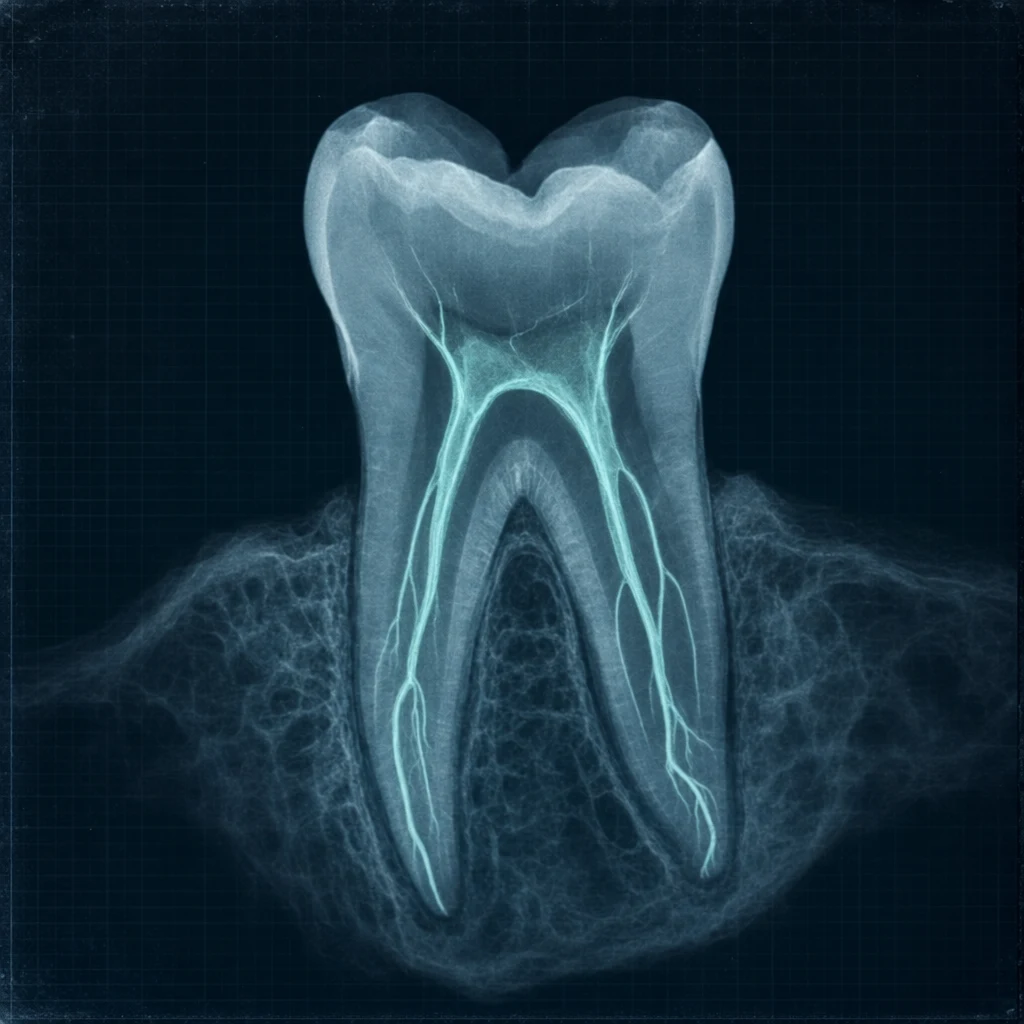

신경치료는 충치·외상·치아 균열 등으로 치아 안쪽 신경(치수)이 감염·염증을 일으켰을 때 진행하는 시술입니다.

신경관은 매우 가늘고 분지가 복잡합니다. 일부 부위에 감염이 남아있으면 시간이 지나면서 다시 활성화됩니다. CBCT 또는 미세현미경 검사로 확인 가능합니다.